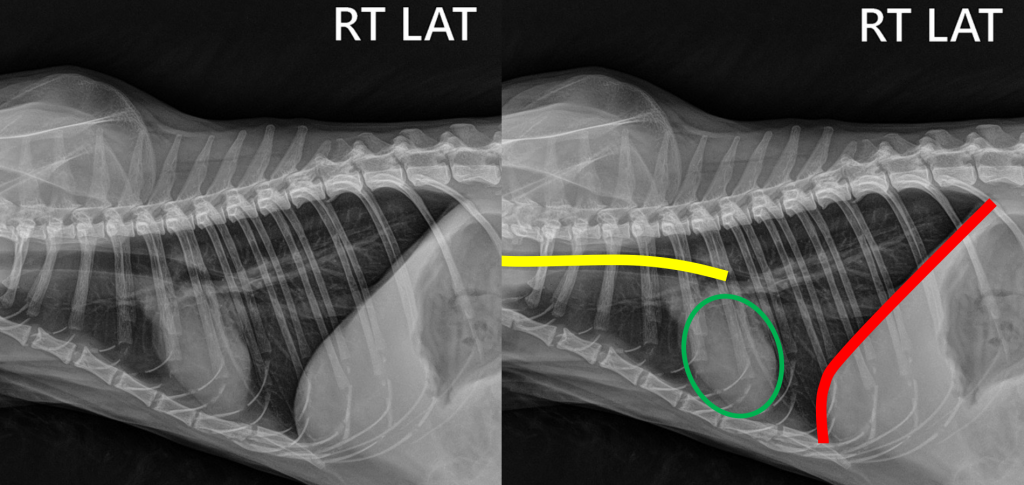

• Рентген грудной клетки. Проводится при возможности! (нужно учитывать, что состояние некоторых питомцем не позволяет выполнить данное исследование). На рентгене будет заметен «эффект матового стекла» в грудной полости, не видны контуры сердца, четко виден контур трахеи и легких, легкие смещены относительно нормального положения.

Рис. 1,2. Рентген грудной полости в норме. Четкая визуализация контура диафрагмы (красное), контура легких, трахеи (желтое), сердца (зеленое).

Рис. 3,4. Рентген грудной полости при гидротораксе. Четкая визуализация трахеи (желтое). Контур легких сдвинут дорсо-каудально (синее), объем легких уменьшен. Эффект матового стекла (красное). Нет четкого контура диафрагмы.